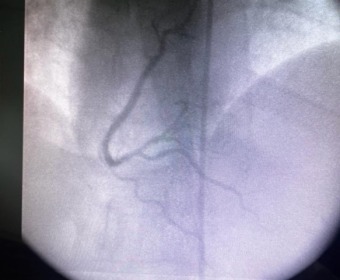

HITO HISTÓRICO EN GESELL: REALIZAMOS EL PRIMER CATETERISMO EN EL HOSPITAL MUNICIPAL "ARTURO ILLIA"

En un hecho trascendental para la salud geselina, el Hospital Municipal "Arturo Illia" llevó a cabo el primer cateterismo gratuito de la ciudad a un paciente de 39 años de edad, que carece de obra social.

El procedimiento de cateterismo cardíaco es una herramienta fundamental para diagnosticar con precisión enfermedades en las arterias del corazón. Permite identificar obstrucciones en las venas o arterias, determinando su grado de afectación y gravedad. La información proporcionada por esta técnica es esencial para comprender la relevancia de las afecciones cardíacas y definir el tratamiento apropiado a cada caso.

Este logro es el fruto de un convenio gestionado por el secretario de Salud, Miguel Angel Muñoz, entre la Municipalidad y el Servicio de Hemodinamia de la Clínica del Sol, donde se articula el trabajo público con el privado para el bienestar de la población. Cabe destacar que este hito tan importante para Villa Gesell se da en el marco del cumplimiento de 9 meses de gestión por parte del doctor Muñoz al frente de la Secretaría. Esta iniciativa representa un nuevo paradigma en la salud de Gesell, siendo un avance único en la región. La innovación y el compromiso con la salud de la población se manifiestan en este importante paso hacia adelante en la atención médica local.